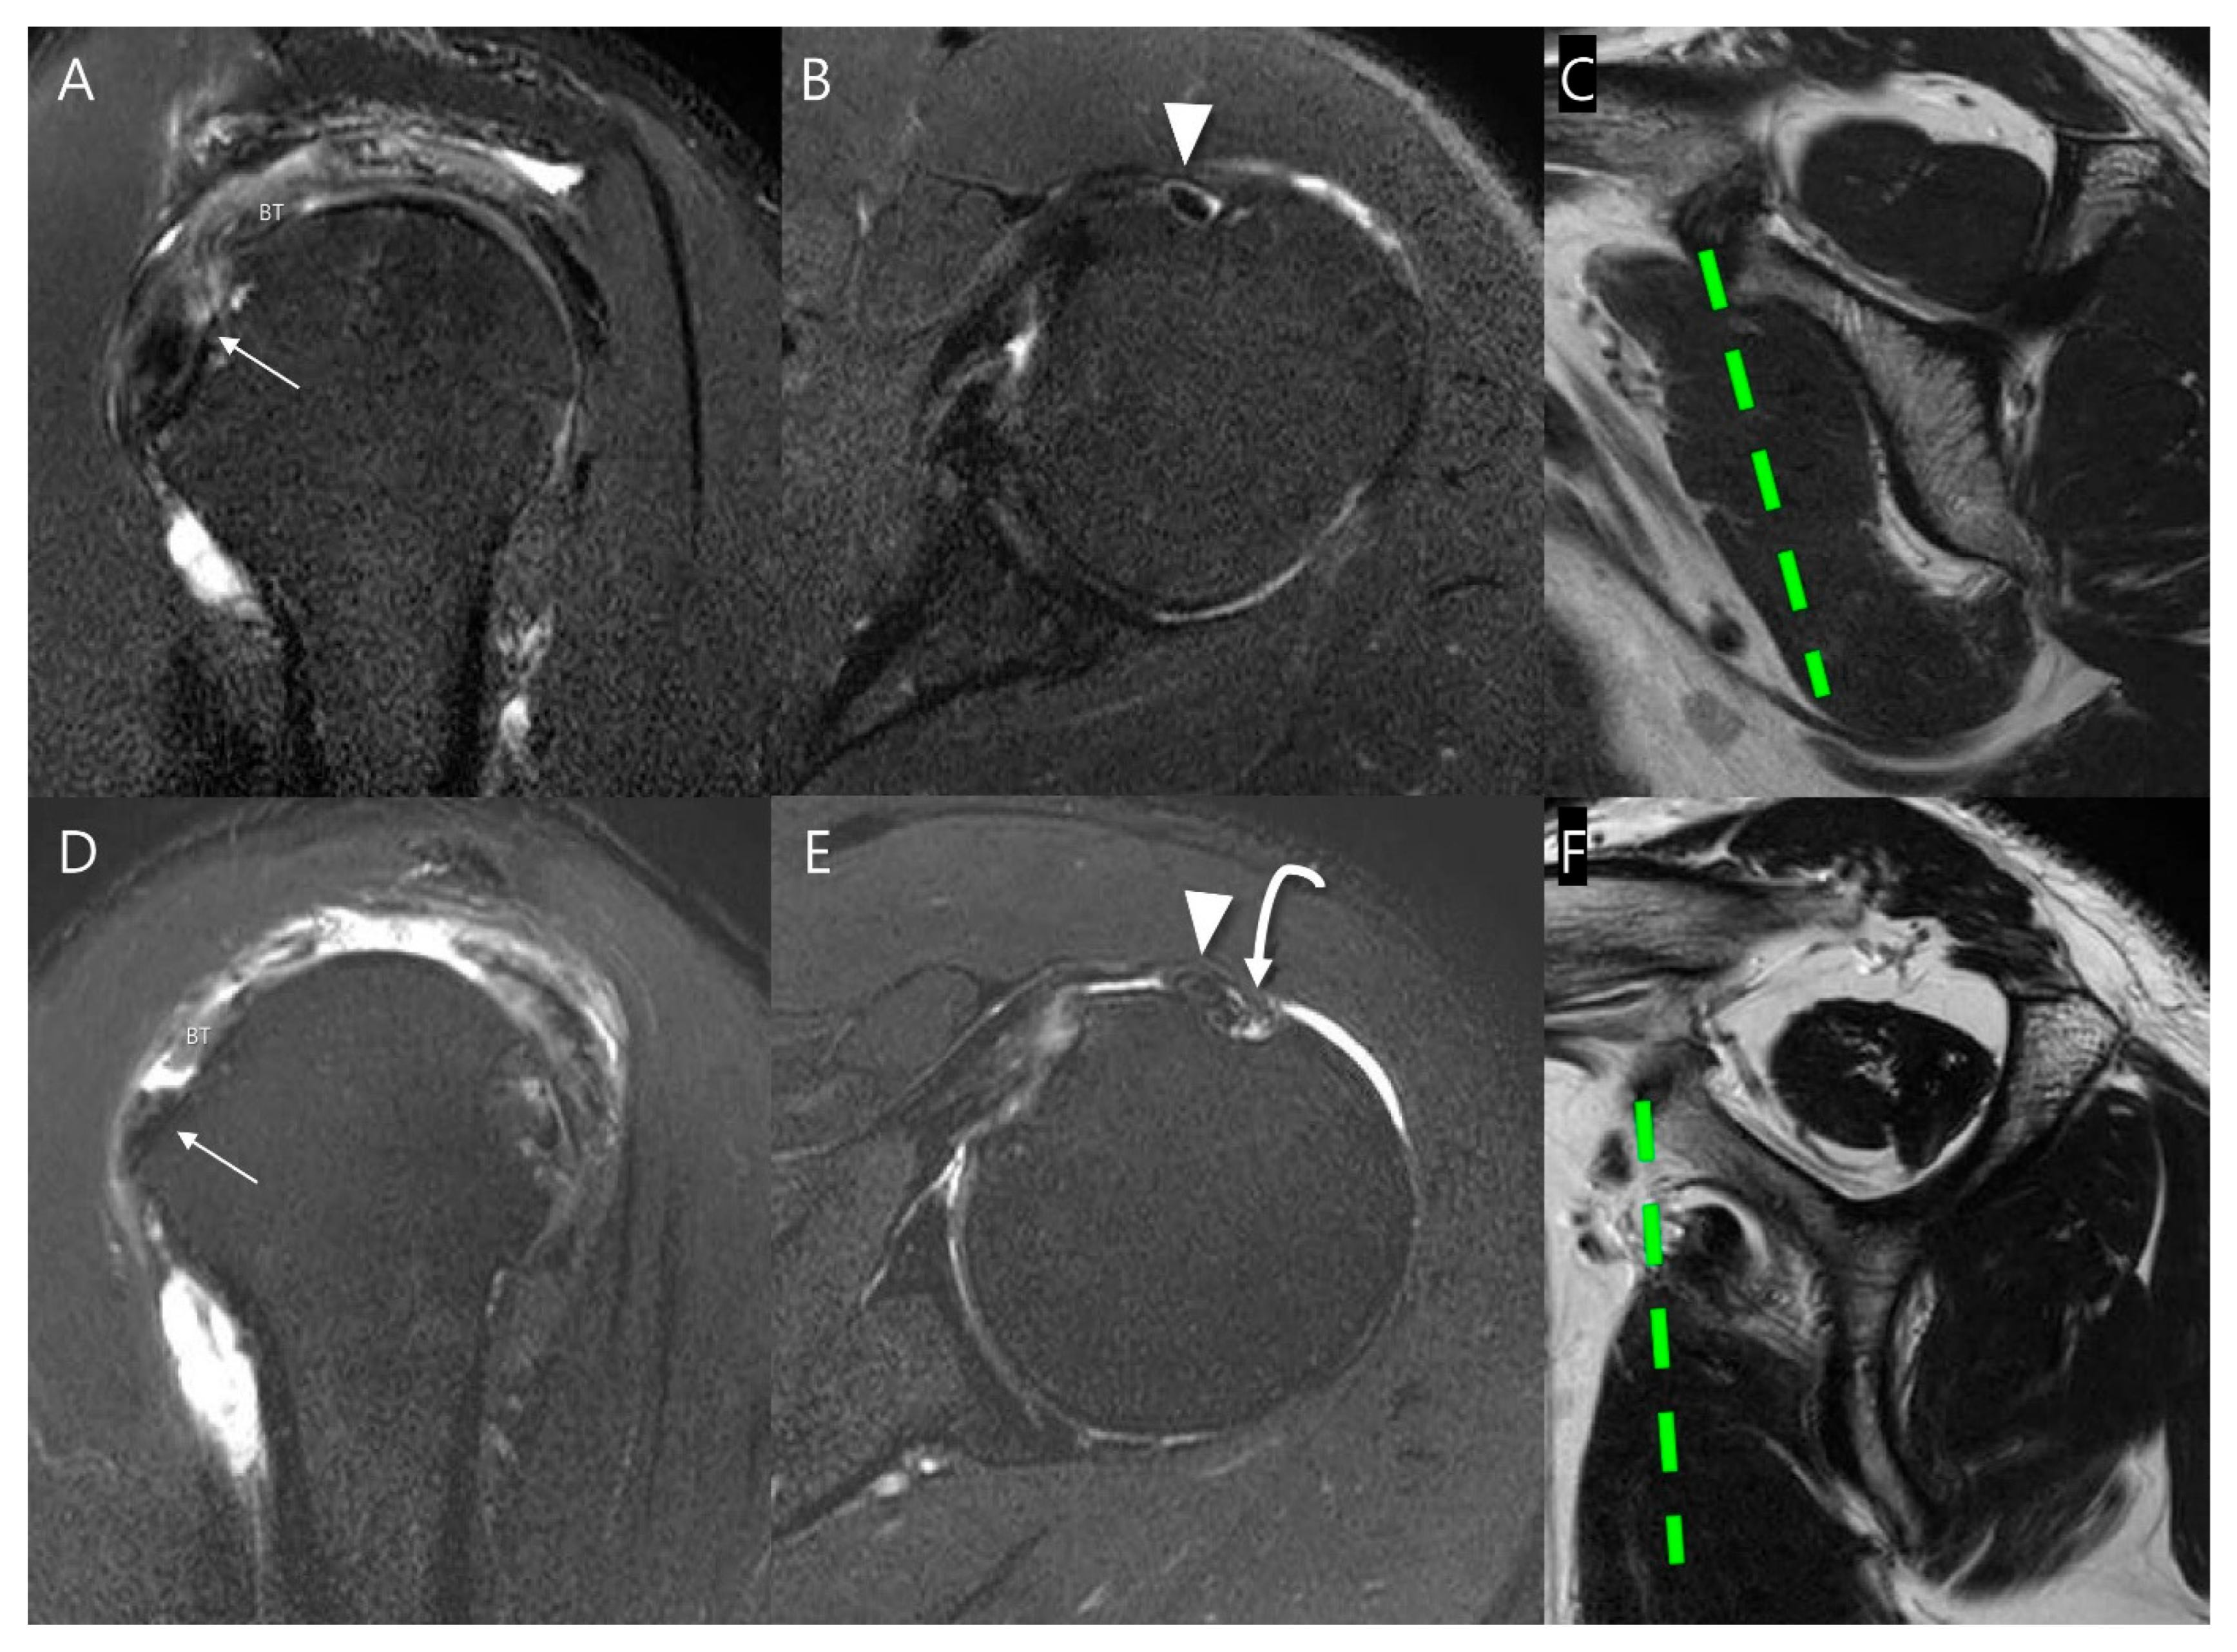

Figure 3.

Subclassification of Lafosse type 1 subscapularis tendon (SSC) partial thickness tears according to the Yoo and Rhee classification. On T2-weighted oblique sagittal images with fat suppression, (A) a normal SSC footprint shows a thin tendinous slip (arrow) in the superior portion, which is closely related to the stability of the biceps tendon (BT). Note that most partial thickness tears (Lafosse type 1) originate from this tendinous slip. (B) Yoo type I tear shows fraying or a longitudinal split at the leading edge (arrow). (C) Yoo type IIA tear is defined as the detachment of less than 50% of the first facet (arrow). (D) Yoo type IIB tear is defined as the detachment of more than 50% of the first facet (arrow).